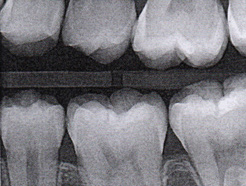

Fig 6. Three thin soft dental picks were used simultaneously for SDF proximal surface saturations in a teenaged patient (Fig 3). After 60 seconds, the treated regions were covered with 5% fluoride varnish (Fig 4). A comparison can be seen of pre-SDF-treatment bitewing films (Fig 5) and 8-month post-SDF bitewing films (Fig 6) for the patient shown in Fig 3 and Fig 4. Radiolucencies were similar or improved, except for contact of maxillary first and second molars.

Fig 5. Three thin soft dental picks were used simultaneously for SDF proximal surface saturations in a teenaged patient (Fig 3). After 60 seconds, the treated regions were covered with 5% fluoride varnish (Fig 4). A comparison can be seen of pre-SDF-treatment bitewing films (Fig 5) and 8-month post-SDF bitewing films (Fig 6) for the patient shown in Fig 3 and Fig 4. Radiolucencies were similar or improved, except for contact of maxillary first and second molars.

Fig 3. Three thin soft dental picks were used simultaneously for SDF proximal surface saturations in a teenaged patient (Fig 3). After 60 seconds, the treated regions were covered with 5% fluoride varnish (Fig 4). A comparison can be seen of pre-SDF-treatment bitewing films (Fig 5) and 8-month post-SDF bitewing films (Fig 6) for the patient shown in Fig 3 and Fig 4. Radiolucencies were similar or improved, except for contact of maxillary first and second molars.

Interproximal insertion of SDF is demonstrated in different patients in Figure 3 through Figure 11. Various diameters and brands of soft dental picks may be used depending on the closeness of the proximal surfaces and ease of insertion; for example, some picks are designed for use in wider spaces between teeth. This protocol also offers versatility. Figure 3, for example, shows the simultaneous use of three thin soft dental picks to saturate proximal surfaces with SDF in a teenaged patient; the treated regions were subsequently covered with fluoride varnish (Figure 4). This patient was initially treated in April 2019 (Figure 5), with an identical re-application 3 months later. As shown in Figure 6, the December 2019 bitewing film revealed good results with the possible exception of the contact regions of the maxillary first and second molars. New SDF application was completed in the December appointment.

The senior author's (TPC) private practice experience with soft-tip insertion of SDF into contacting proximal surfaces of teeth is that most beginning proximal surface caries lesions cease to progress, as evidenced by subsequent bitewing radiographic comparisons (Figure 3 through Figure 6, Figure 12 through Figure 18). The chances for success vary, however, depending on frequency of application, subsequent flossing by patients or adults flossing younger children, diet control, individual mouth chemistries, and use of fluorides for the topical effect. It must also be emphasized that office staff should make extensive efforts to inform children and parents that subsequent daily flossing is needed to accompany SDF treatments; otherwise, SDF applications will only delay the inevitable progression of caries. Flossing methods should be demonstrated for patients and for parents so they may see how to floss younger children. Showing them enlarged graphic photographs of flossing results may be helpful in this regard. Parents and patients should be made aware that if interproximal dental plaque accumulations persist without daily interruption by flossing, the acid insult will eventually take its toll on the proximal surfaces and caries lesions will progress to the point where restorative intervention may be required.